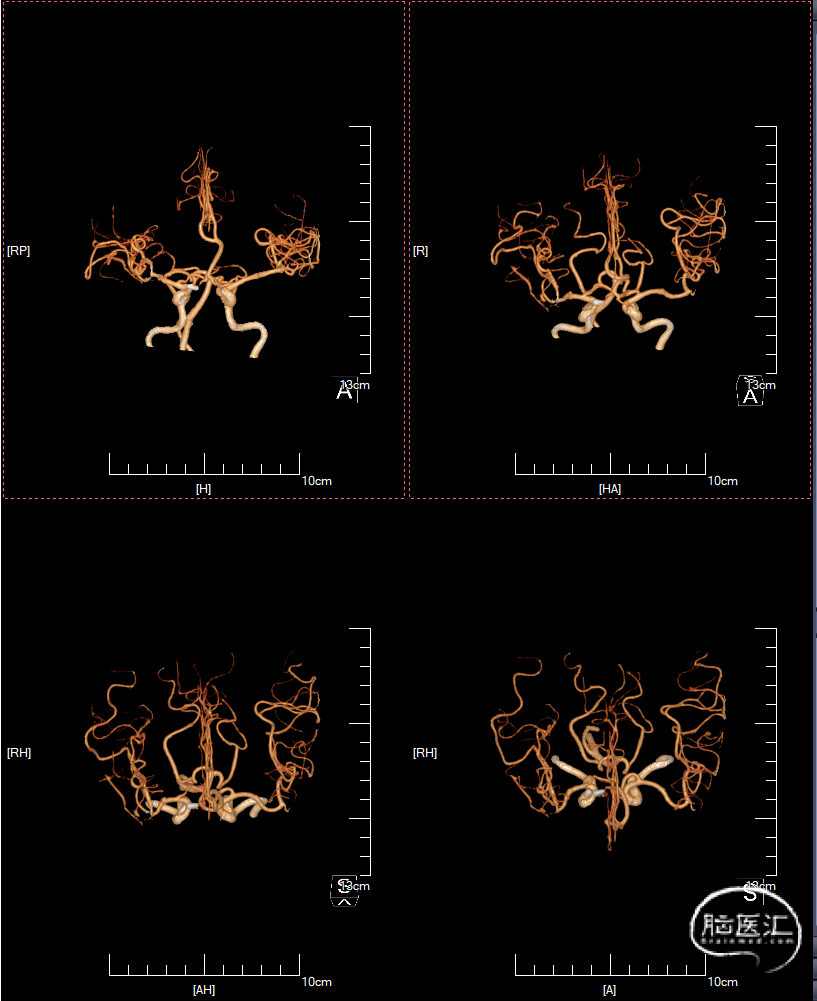

入院后行DSA检查,显示右侧颈内C6-7段动脉瘤右侧大脑中动脉M1分叉动脉瘤。

C6-7段动脉瘤位于颈内动脉上壁,指向内上方,考虑血泡样动脉瘤,结合蛛血位置,及动脉瘤形态、大小,考虑颈内动脉血泡为责任动脉瘤。

术后10天复查CTA: